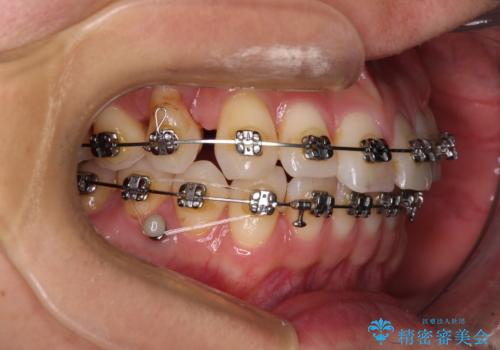

咬合平面改善のため、アンカースクリューを多用し、ワイヤー装置にて矯正治療を行うこととしました。

動きにくい歯はやはり動きにくく、咬み合わせ改善に時間を要しましたが、患者様には大変満足していただけました。